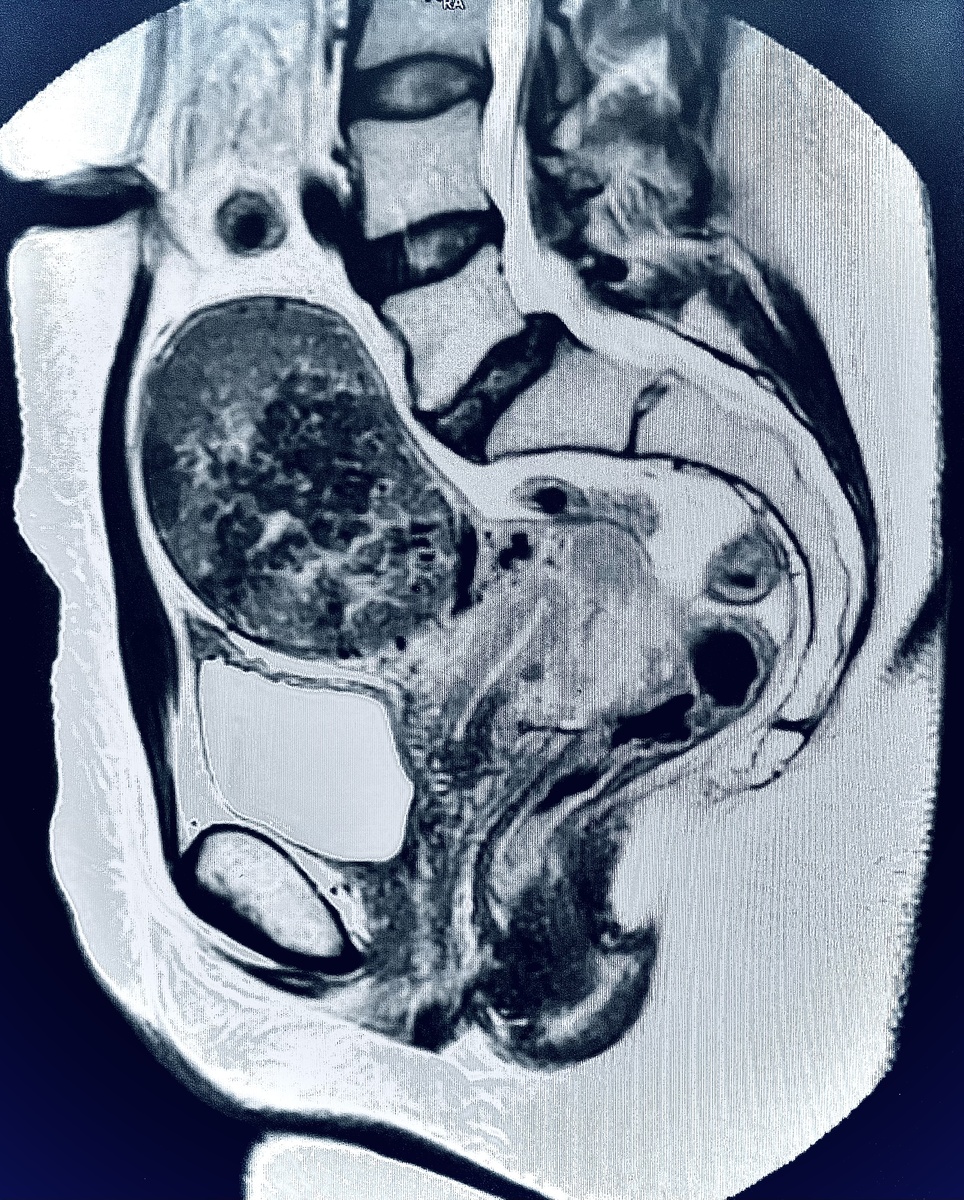

МРТ органов малого таза